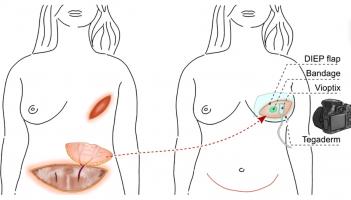

CICATRISATION : Le pansement liquide qui mesure l’oxygénation tissulaire